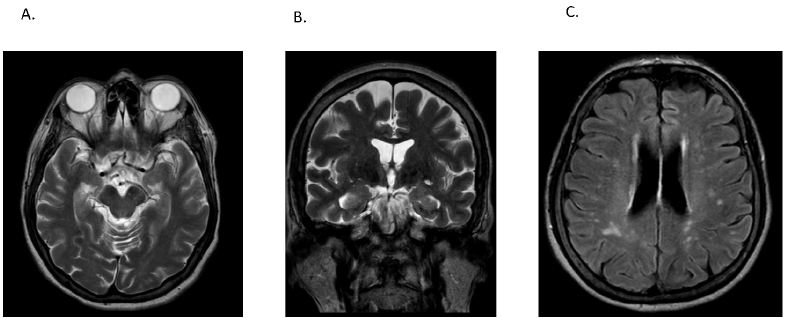

En los análisis paraclínicos, se solicitó perfil tiroideo (TSH 0.19 mUI/L, T4 libre 1.4 nmol/L, T3 libre 3.27 nmol/L), que reveló anticuerpos antitiroideos tiroglobulínicos positivos (301.36 UI/mL). En el análisis del líquido cefalorraquídeo (LCR) se encontró hiperproteinorraquia acelular con bandas oligoclonales positivas, sin identificación de anticuerpos (test inmunoblot EUROLINE para síndrome paraneoplásico amfifisina, CV2, PNMA2, Ri, Yo, Hu, Recoverina, SOX1, Titina, Zic4, GAD65 y test de inmunofluorescencia indirecta en células HEK293 NMDA, AMPA 1 y 2, GABA B1/B2, LGI2CASPR2, DPPX). La resonancia magnética con gadolinio no mostró lesiones intracraneales sugestivas de procesos neoplásicos secundarios (Figura 1), así como la telemetría, que no presentó trazos anormales.

Figura 1 Resonancia magnética cerebral. A) Corte axial en T2 sin evidencia de hiperintensidades a nivel temporal y sin alteraciones volumétricas apreciables. B) Corte coronal en T2 sin evidencia de hiperintensidades a nivel temporal. C) Corte axial en FLAIR con evidencia de múltiples hiperintensidades en sustancia blanca de predominio posterior Fazekas I.

de que dicho riesgo depende del antidepresivo utilizado.16Asimismo, dados los hallazgos en el análisis neurológico y del LCR se consideró que la paciente cursaba concomitantemente un proceso autoinmune (encefalitis autoinmune posible). En un nivel neuroimagenológico, se evidenciaron hiperintensidades de predominio occipital, sin la presencia de procesos agudos o subagudos concomitantes. Debido a esto, se contempló la posibilidad de una manía vascular.17 No obstante, existen limitaciones en el uso clínico de este concepto debido a la poca disponibilidad de reportes de caso, los cuales no siempre presentan una relación entre el desarrollo de síntomas neurológicos y los síntomas maniformes, y tampoco criterios uniformes sobre qué considerar como lesiones significativas. Debido a que la paciente tenía lesiones caracterizadas como Fazekas I, y dada la posibilidad de factores de confusión debido a la asociación entre factores de riesgo cardiovascular, la manía de inicio tardío18 y las hiperintensidades de sustancia blanca, no específicas del síndrome maníaco,17 esto no se consideró como un factor etiológico sino de vulnerabilidad.